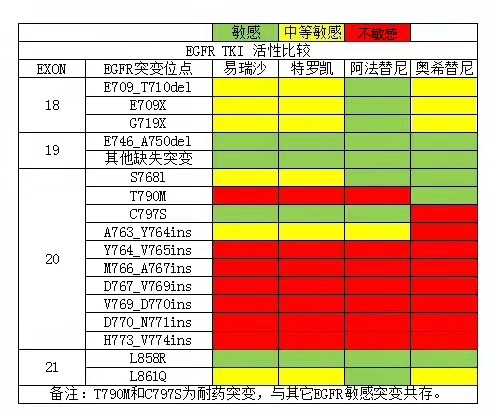

肺癌是一种复杂多变的疾病,其中非小细胞肺癌占据了约85%的病例。在这类肺癌中,常见的亚型有肺腺癌和肺鳞癌。研究人员发现,肺癌的发生和基因突变有着很大联系,其中表皮生长因子受体(EGFR)突变是一种常见的基因突变,尤其在肺腺癌中频率较高。对于亚裔非吸烟患者,EGFR突变的发生率更是高达40%至50%,而EGFR突变中又包括18位点G719X突变、19缺失突变、20位点S7681突变,21位点L858R突变、21位点L861Q突变等。这些位点对应使用的靶向药不同,例如亚洲不吸烟的女性,通常是19缺失突变和21位点L858R突变,此时使用易瑞沙、特罗凯、奥希替尼通常效果比较好,而肺鳞癌男性患者中,出现18位点G719X突变、20位点S7681突变、21位点L861Q突变等突变的情况比较多,此时使用阿法替尼效果比较好。

- 肺癌第一代EGFR靶向药:易瑞沙(吉非替尼)、特罗凯(厄洛替尼)、凯美纳(埃克替尼)

- 肺癌第二代靶向药:阿法替尼

- 肺癌第三代靶向药:泰瑞沙(奥希替尼)、阿美替尼、伏美替尼、贝福替尼

2.肺癌靶向药并不是按照一代耐药后使用二代,二代耐药后再使用三代的顺序,而是根据基因检测结果判断使用哪一种。

3.二代阿法替尼相比一代,与EGFR的结合力更强,且作用靶点更广泛。因此二代阿法替尼在治疗效果上有所提升,同时能够覆盖一代药物未能覆盖的突变类型。